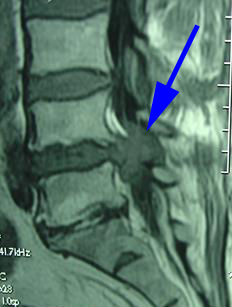

Cauda equina syndrome is a rare but serious condition that is deemed a medical surgical emergency. Cauda equina syndrome may have long-lasting effects if not addressed right away.

The gold standard of care for cauda equina syndrome is surgery to decompress the spinal nerves. This may involve the removal of disc material or disc fragment that has entered the spinal canal space. How soon does this surgery need to be done? The medical research literature is filled with recommendations of “immediately” to discussions of positive results similar to outcomes of immediate surgical interventions when the surgical intervention happened 1 to 3 months after the onset of cauda equina symptoms. The best course of action is immediate physician evaluation and recommendation.